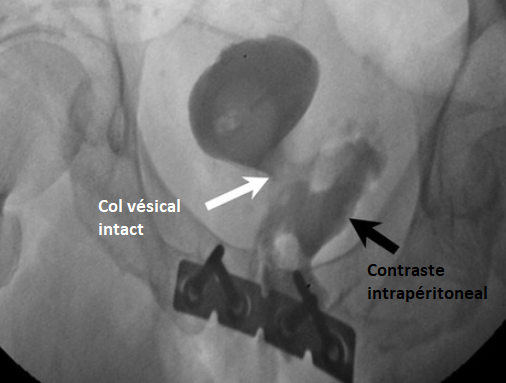

Classification de Goldman

Goldman I

Goldman II

Godlman III

Goldman IV

Goldman IVa

urètral urethral urètrhal uretral urètre urèthre trauma traumatisme choc lésion fracture rutpure

urètral urethral urètrhal uretral urètre urèthre trauma traumatisme choc lésion fracture rutpure